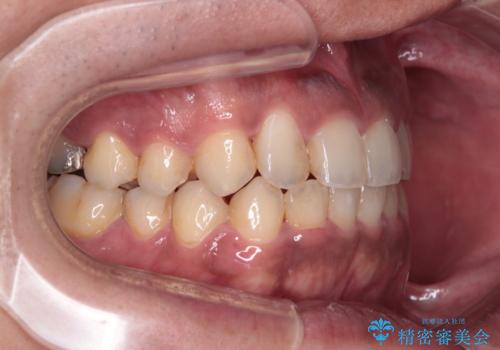

- 前歯のデコボコを気にして来院された患者様です。

前歯が90度近く捻れていたため、しっかりと治すことを考えるとワイヤー矯正の方がおすすめではありましたが、本人の希望によりインビザラインを用いて矯正治療を行うこととしました。

インビザラインは、十分な装着時間が達成されると前歯のデコボコをしっかりと改善できますが、1日の装着時間が20時間に達しなくなると、不十分な仕上がりとなるため、しっかりと装着するよう指示をしました。

途中2年強の来院がなく、改善されていたデコボコが元に戻ったり、装着時間が不足しており前歯のデコボコは十分に改善することはできませんでしたが、5年間の有効期限内で可能な限り歯列を整えることができました。